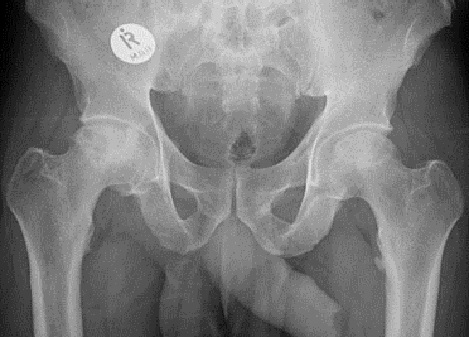

Fig1. - 'Open book' fracture of the pelvis.

Fig1. - Treated with open reduction and internal fixation.